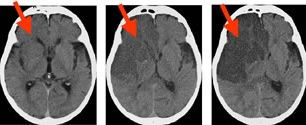

脳梗塞の検査

脳梗塞で脳細胞が傷つくと血管内でアクロレインという物質が出ます。それと同時にいくつかの炎症物質も出現します。これらの数値と年齢などを総合的に判断し、かくれ脳梗塞を検出できる検査をアミンファーマ社が開発しました。 ・低リスク群 約16% ・境界群 約70%...